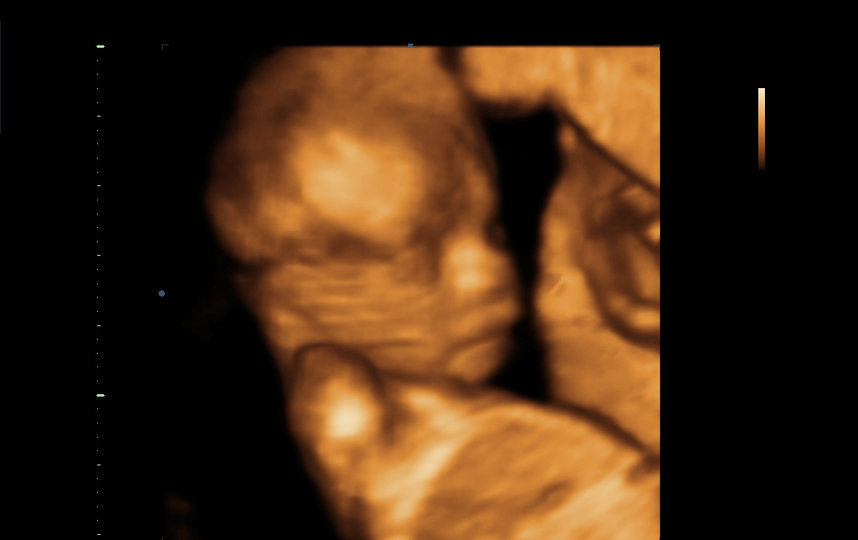

– Мама – моя лучшая подруга! – воскликнула Бреанна. – Я плачу каждый раз, когда вижу малыша на ультразвуке. Это невероятные эмоции! Я люблю трогать её живот. Она каждый раз кричит, чтобы я поскорее к ней бежала, и даёт почувствовать, как девочка толкается. Едва слыша, как мама зовёт меня, я бросаю всё и мчусь к ней. Это потрясающе и нереально.

Будущая радость семьи Локвуд.

предоставила Бреанна Локвуд